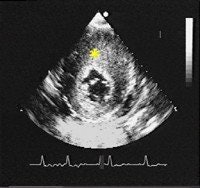

| HCM is the most common cause of sudden cardiac death in young athletes and people younger than 30 years of age. In a normal heart, the heart walls are 11 mm or less in thickness (above and below). |

| Patients with HCM have a characteristic thickening of the heart walls that can range from 14-60 mm. Particular thickening of one part of the heart, the interventricular septum, is characteristic of patients with HCM. The thick interventricular septum is marked with an asterisk. Images courtesy of the Hypertrophic Cardiomyopathy Program, St. Luke's-Roosevelt Hospital Center, New York City. |